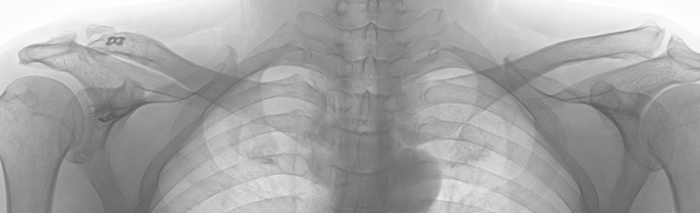

The following X-ray is taken 2 years after the operation.

It is clearly seen that the right acromioclavicular is deformed as it took 20 years since the initial dislocation happened. I only performed to clamp the two joints with autograft ligaments and metal end-buttons as the deformation has been already progressed at the time of surgery.